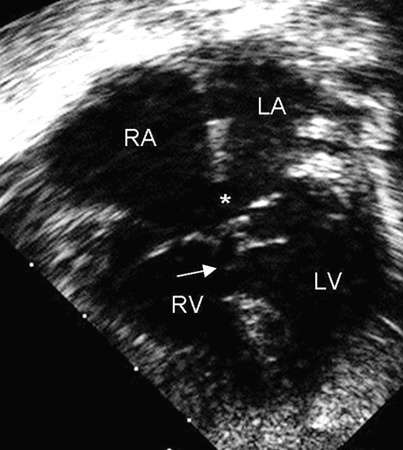

Represents 4% to 5% of all CHDs and is found in 40% of children with Down's syndrome.[32] This defect is also called endocardial cushion defect or atrioventricular (AV) canal defect. Endocardial cushions close the ostium primum and form portions of the AV valves and the ventricular septum. AVSDs may be partial or complete; 1 type of a partial AVSD is a primum atrial septal defect (ASD). A complete AVSD consists of a primum ASD and a contiguous inlet ventricular septal defect (VSD).[Figure caption and citation for the preceding image starts]: Apical 4-chamber echocardiographic image of complete AVSD. Note the ostium primum ASD (*) and the contiguous inlet VSD (arrow). (RA) right atrium; (LA) left atrium; (RV) right ventricle; (LV) left ventricleImage courtesy of Patrick W. O'Leary, MD [Citation ends].